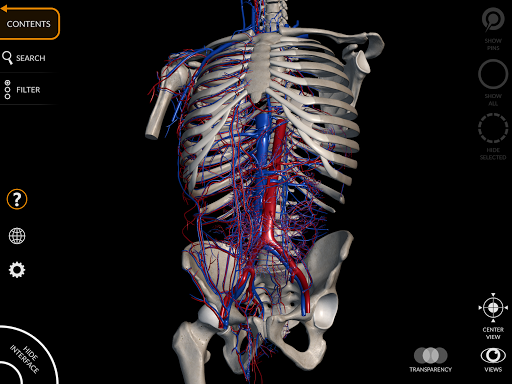

• Серцево-судинна система

• Фільтр, щоб приховати або відобразити кожну систему

• Функція прозорості

• Серцево-судинна система